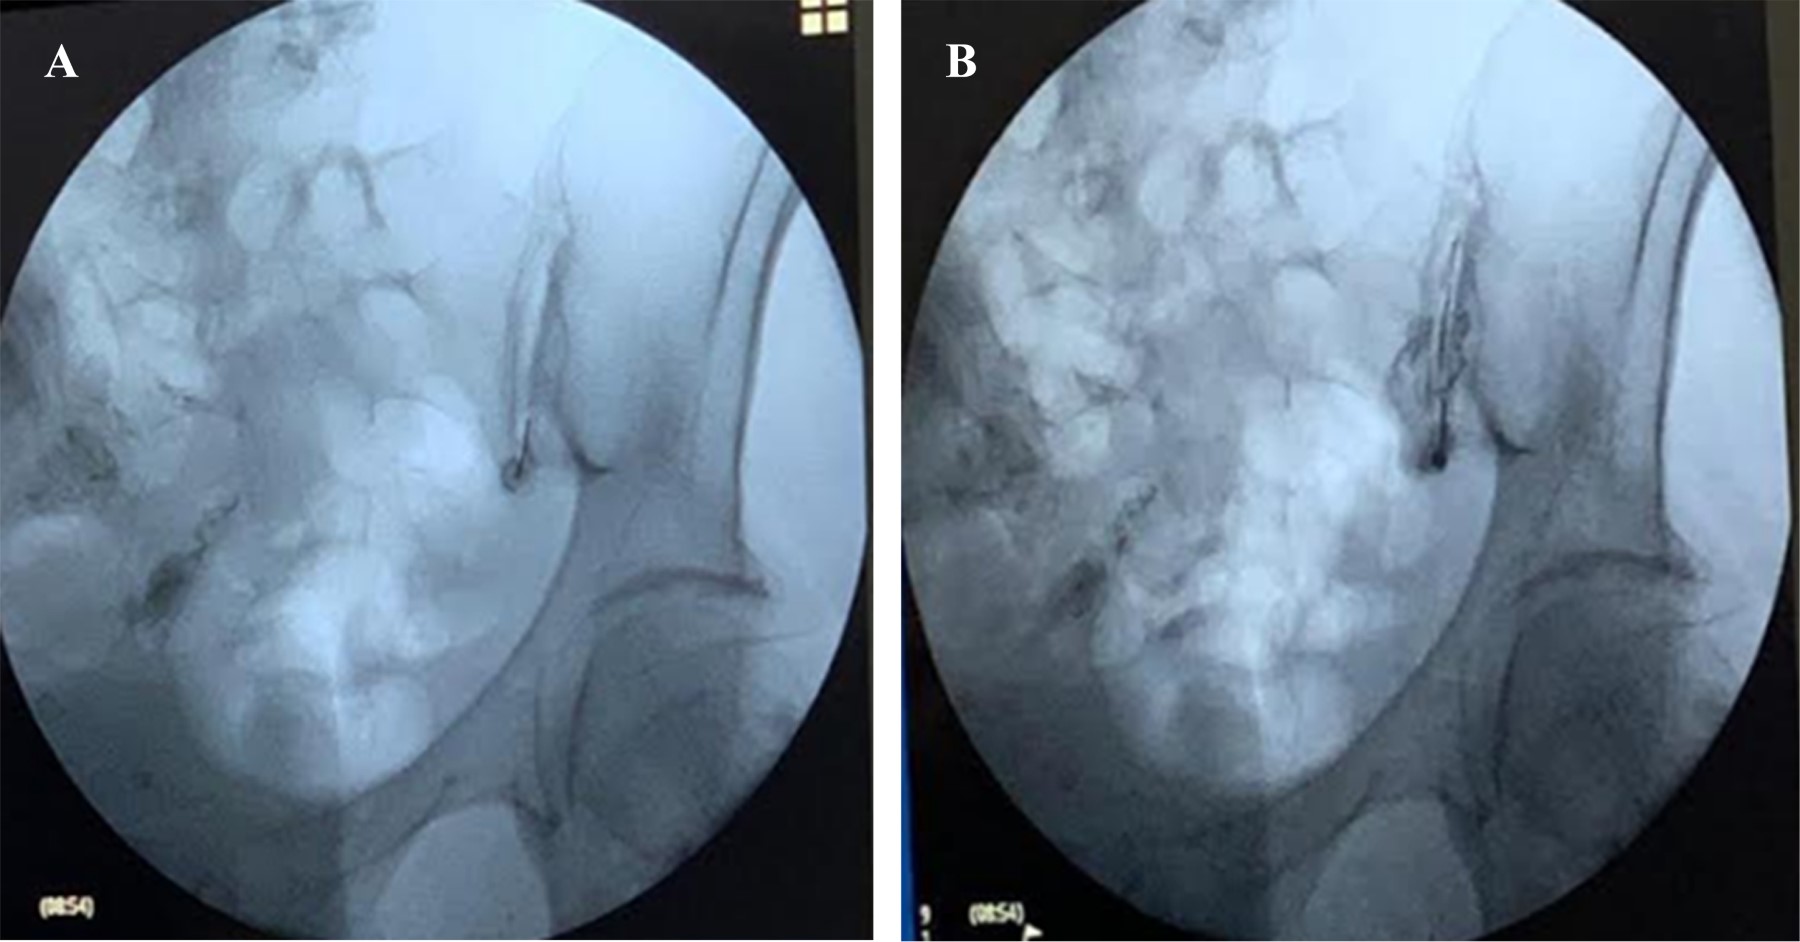

Monitorization included continuous electrocardiography and O2 saturation plus non-invasive blood pressure at 3-min intervals. In a sterile operating room, patients were prone on the surgical table with a cushion under the lower abdomen to reduce lumbar lordosis and the needle entry point was driven by C-arm fluoroscopy. The corrected entry point was conducted by 0.5 ml of 300 mg/ml non-iodate iohexol contrast injected into the needle (Figure 1). Thereafter, a combination of 5 mg dexamethasone plus 20 mg lidocaine (3 ml) was dispensed IA, combined to periarticular SIJ administration of the same amount (10 mg dexamethasone + 20 mg lidocaine, final 3 ml).

Figure 1